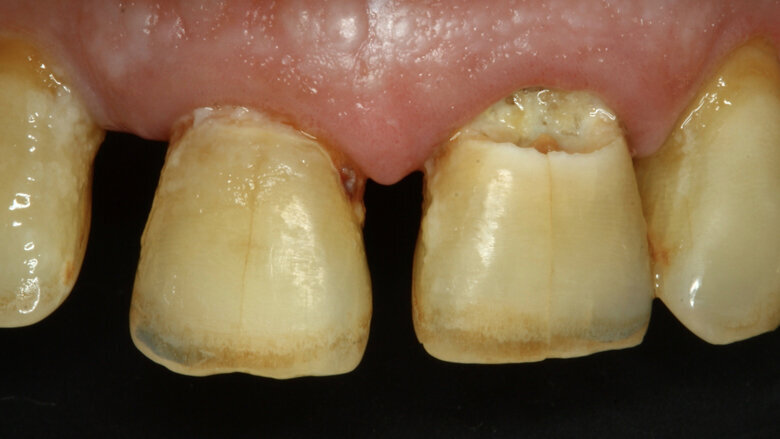

Figura 1. Lesiones de caries cavitadas en dentina activa (ICDAS 5) en dientes 11 y 21 en paciente másculino (Caso 1).

Paciente masculino de 65 años de edad se presenta al consultorio con lesiones de caries cavitadas en dentina activa (ICDAS 5) en dientes 11 y 21 (Figura 1). La lesión de la pieza 21 es extensa, mediante examen radiográfico y pruebas de vitalidad se diagnostica ausencia de compromiso pulpar. Como la lesión se extiende infra-gingivalmente, se opta por colocar dos hilos retractores 000 y 00 (Ultrapack, Ultradent, EE UU) y aislamiento absoluto con hilo dental tipo teflón y un clamp para anteriores (Figuras 2 y 3). Se inicia el procedimiento de remoción químico-mecánica utilizando un agente enzimático (Brix3000, Brix Medical Science, Argentina) durante 2 minutos (Figura 4). Utilizando curetas (Maillefer, EE UU) se elimina la dentina infectada (Figura 5) y el esmalte sin soporte dentinario (Figura 6) es eliminado con una fresa multilaminada (Figura 7) para mejorar el mimetismo y la adhesión al esmalte. Se complementa la instrumentación mecánica en el límite amelo-dentinario (Figuras 8 y 9).